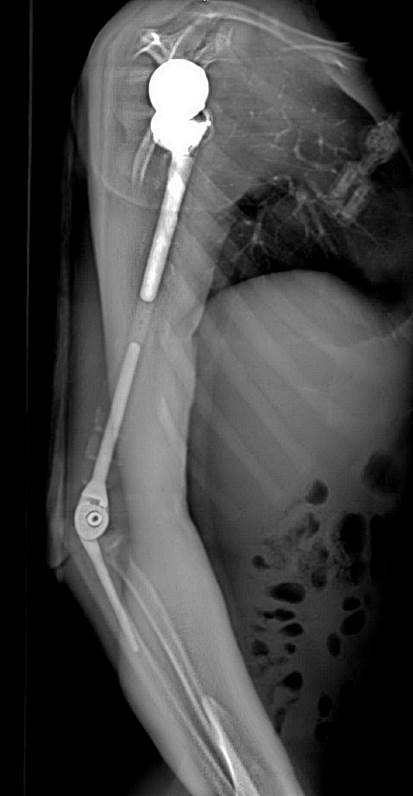

Ảnh chụp X-quang tay phải của bệnh nhân sau khi phẫu thuật thay xương toàn bộ cánh tay

Nhóm phẫu thuật đã lên kế hoạch sử dụng các công nghệ trong tái tạo xương hiện đại nhất hiện nay bao gồm tái tạo lại cấu trúc khớp vai, cấu trúc khớp khuỷu bằng vật liệu hợp kim titan. Đặc biệt, đội ngũ bác sĩ của Trung tâm đã có một quyết định định táo bạo: không sử dụng hoàn toàn vật liệu kim loại mà chế tạo phần thân xương cánh tay sử dụng công nghệ in 3D vật liệu polyme sinh học (PEEK). Vật liệu này do phòng nghiên cứu ứng dụng công nghệ in 3D của Đại học VinUni sản xuất, giúp kết nối phần khớp vai và khớp khuỷu với nhau, đồng thời phục hồi lại điểm bám của các gân cơ quanh cánh tay. Đây được coi là một quyết định đầy tính sáng tạo dựa trên những nghiên cứu và thử nghiệm chuyên sâu từ nhiều ca bệnh đã thành công của ê-kíp phẫu thuật.

Đặc biệt, công nghệ in 3D được coi là công nghệ duy nhất hiện nay mang lại khả năng cá thể hóa các chi tiết cấy ghép. Nhờ công nghệ này, cả 3 phần của xương cánh tay nhân tạo đều được "thiết kế riêng" theo đúng kích thước cánh tay thật của bệnh nhân, đồng thời có các điểm cố định giúp khôi phục lại hệ thống gân cơ bám xương. Trước khi sản xuất, tất cả những thiết kế này đều được thử nghiệm mô phỏng khả năng vận động, chịu lực trên máy tính. Nhờ vậy, xương nhân tạo sau ghép sẽ tương thích tối đa, "hoàn toàn vừa vặn" với cơ thể người bệnh và thời gian phục hồi chức năng vận động của cánh tay sẽ được rút ngắn đáng kể.